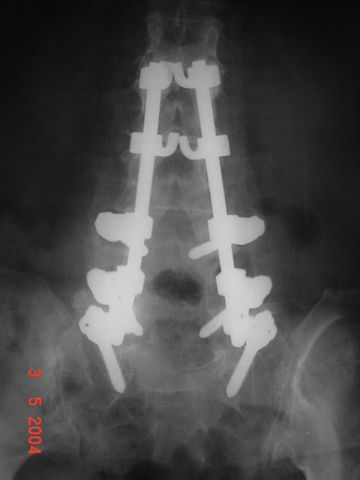

Paciente del sexo femenino de 79 años de edad.

Por problemas en la columna laminectomía y fijación.

Es la tecnología puesta a la orden de mejorar calidad de vida de los pacientes.